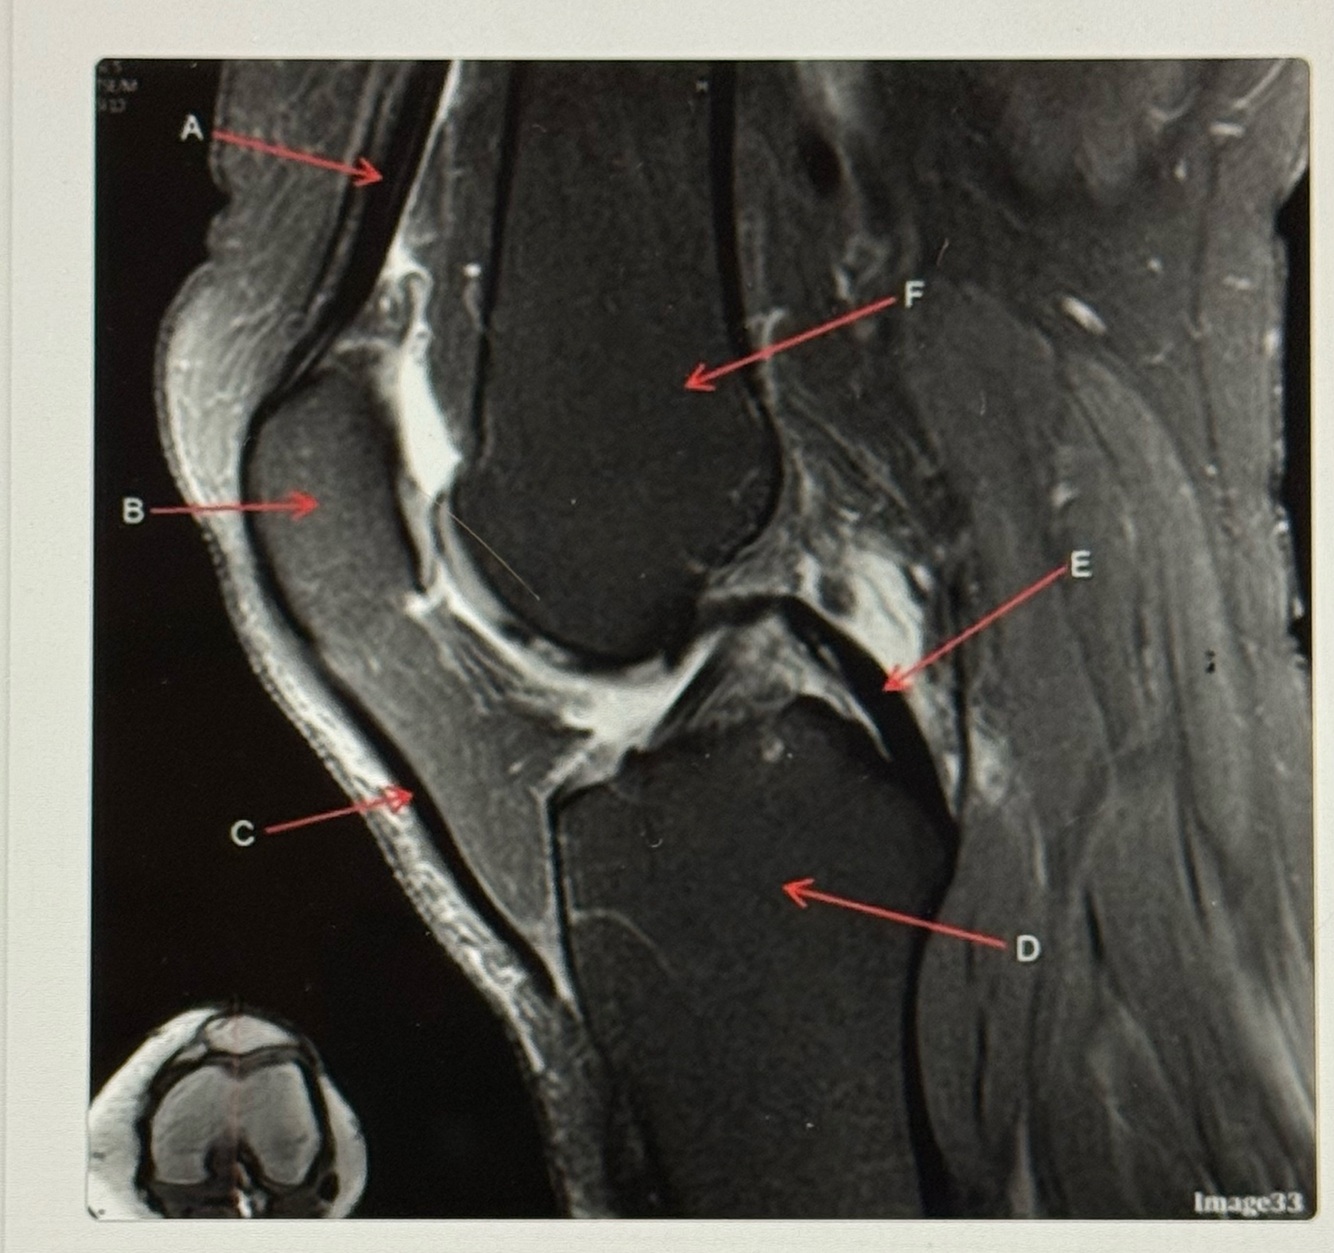

Letter B points to the

Femur

Letter A points to the

Patella

Letter C points to the

Anterior horn of lateral meniscus

Letter D points to the

Tibia

Letter E points to the

Head of the fibula

Letter F points to the

Posterior horn of the lateral meniscus

Patellar tendon

Posterior cruciate ligament (PCL)